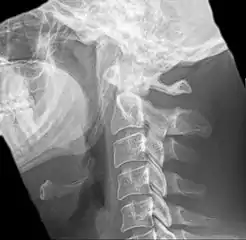

CT scan, coronal section showing bilateral extended styloid process and stylohyoid ligament ossification (incidental finding)

Diagnosis is suspected when a patient presents with the symptoms of the classic form of "Eagle syndrome" e.g. unilateral neck pain, sore throat or tinnitus. Sometimes the tip of the styloid process is palpable in the back of the throat. The diagnosis of the vascular type is more difficult and requires an expert opinion. One should have a high level of suspicion when neurological symptoms occur upon head rotation. Symptoms tend to be worsened on bimanual palpation of the styloid through the tonsillar bed. They may be relieved by infiltration of lidocaine into the tonsillar bed. Because of the proximity of several large vascular structures in this area this procedure should not be considered to be risk free.

Imaging is important and is diagnostic. Visualizing the styloid process on a CT scan with 3D reconstruction is the suggested imaging technique.[12] The enlarged styloid may be visible on an orthopantogram or a lateral soft tissue X ray of the neck.